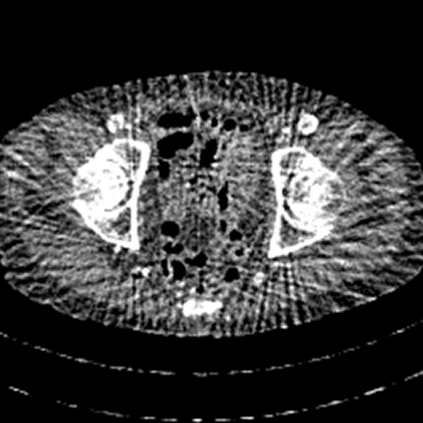

Sparse-view computed tomography (CT) -- using a small number of projections for tomographic reconstruction -- enables much lower radiation dose to patients and accelerated data acquisition. The reconstructed images, however, suffer from strong artifacts, greatly limiting their diagnostic value. Current trends for sparse-view CT turn to the raw data for better information recovery. The resultant dual-domain methods, nonetheless, suffer from secondary artifacts, especially in ultra-sparse view scenarios, and their generalization to other scanners/protocols is greatly limited. A crucial question arises: have the image post-processing methods reached the limit? Our answer is not yet. In this paper, we stick to image post-processing methods due to great flexibility and propose global representation (GloRe) distillation framework for sparse-view CT, termed GloReDi. First, we propose to learn GloRe with Fourier convolution, so each element in GloRe has an image-wide receptive field. Second, unlike methods that only use the full-view images for supervision, we propose to distill GloRe from intermediate-view reconstructed images that are readily available but not explored in previous literature. The success of GloRe distillation is attributed to two key components: representation directional distillation to align the GloRe directions, and band-pass-specific contrastive distillation to gain clinically important details. Extensive experiments demonstrate the superiority of the proposed GloReDi over the state-of-the-art methods, including dual-domain ones. The source code is available at https://github.com/longzilicart/GloReDi.